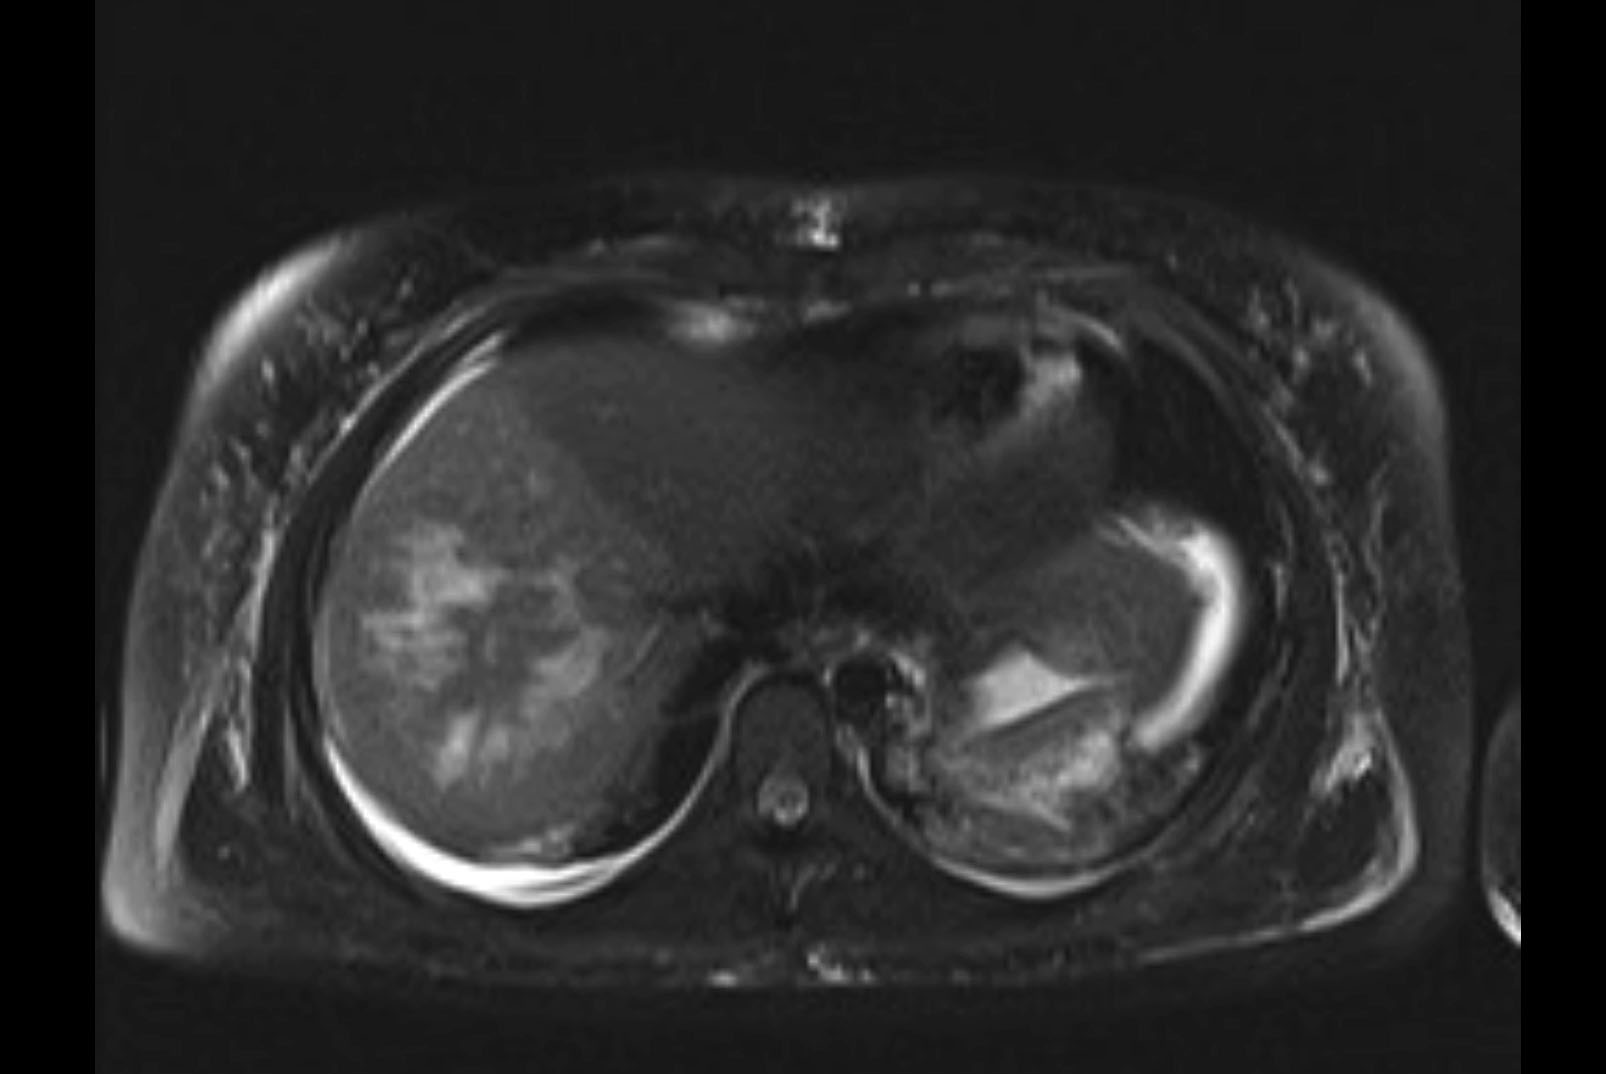

MRI T2